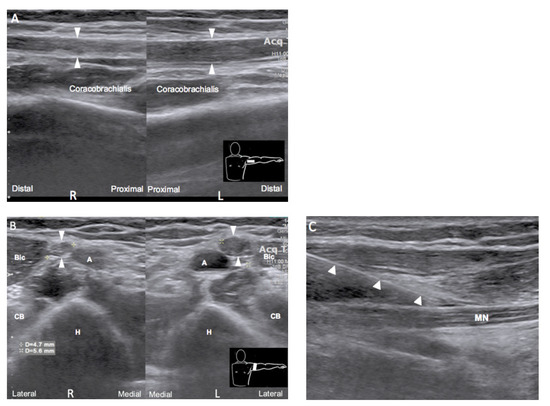

Ultrasound examination was performed simultaneously with electrodiagnostic examination to localize the lesion. A long segment of hypoechoic swelling of the left median nerve was noted from the axillary level until branching to AIN, by side-to-side comparison (Figure 1A,B). Ultrasound-guided hydrodissection of the left median nerve with corticosteroid administration over whole arm from axillary level to elbow (Figure 1C) was performed at the first month after injury after electrodiagnostic examination. The injection was performed twice with a two-week interval. A serial rehabilitation program, two times per week, including neuromuscular electrical stimulation and left forearm flexor strengthening exercises, was established.

Electrophysiological testing and ultrasonography are helpful tools for localizing the lesion in neuropathy. Our case showed decreasing amplitude and conduction velocity when stimulating the median nerve at the elbow and wrist with normal nerve conduction studies over the radial and ulnar nerves, which implies that the influence was on the median nerve rather than on the brachial plexus. The needle EMG suggested that the lesion was an isolated median neuropathy before branching to the FCR and well demonstrated the time course of neuropathy from the acute phase to the reinnervation phase. Nerve ultrasonography further confirmed the lesion at the axilla and showed the classical pattern of neuropathy, which is a hypoechoic and enlarged nerve at the axilla compared with that at the other side. Though MRI is widely used in evaluating brachial plexus injury, ultrasonography has advantages in focal resolution of individual peripheral nerve, accessibility, and without contraindication [10,11]. Meanwhile, ultrasonography can simultaneously being a guided tool for injection intervention.

Figure 1. Comparison of the bilateral median nerve at the axillary level in longitudinal view (A) and transverse view (B) showing hypoechoic and enlarged caliber of the left median nerve. Arrowhead: median nerve. A, axillary artery; H, humerus; Bic, biceps muscle; CB, coracobrachialis muscle. (C) Hydrodissection of the left median nerve at the mid-arm level. Arrowhead: needle; MN: median nerve.